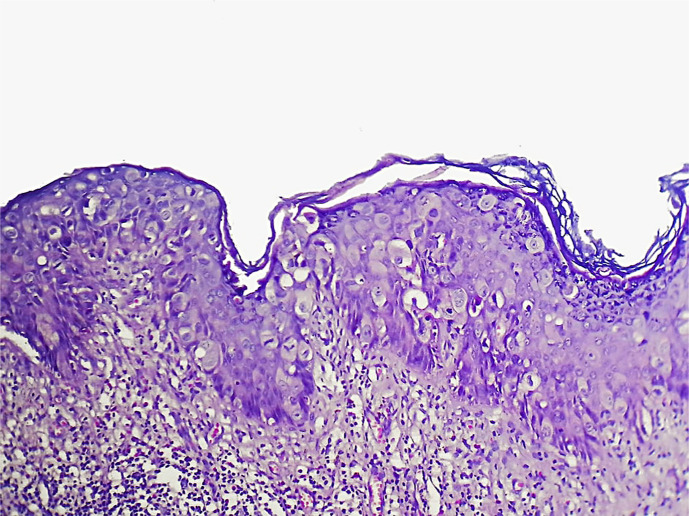

Case report: We present the case of a 64-year-old woman with persistent skin erosion of the left nipple that was unresponsive to multiple topical treatments. Diagnostic evaluation, including mammography and MRI, revealed no invasive malignancy. Nipple biopsy confirmed MPD with underlying in situ ductal carcinoma. The patient underwent lumpectomy with removal of the nipple-areolar complex, followed by radiotherapy, resulting in a favorable outcome.

Discussion: Diagnosis of MPD can be challenging because of its resemblance to benign dermatological conditions. Imaging, particularly mammography and MRI, is essential for assessing the underlying malignancy and surgical planning. Treatment typically involves surgical excision, with breast-conserving therapy considered for localized disease. Early detection significantly improves the prognosis, particularly in the absence of invasive cancer.